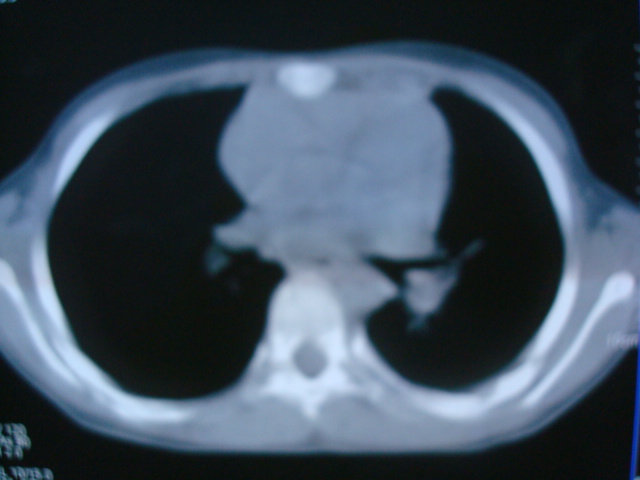

标题: PED0869:男,10岁,肺内多发结节+胸水

男,10岁,左胸痛,发热轻,血象高。后到省级权威医院治疗,病情明显好转,结果几天后公布。老机器,图像质量差,见谅。

考虑血源性肺脓肿或韦氏肉芽肿

考虑血源性肺脓肿

考虑化脓性肺炎。